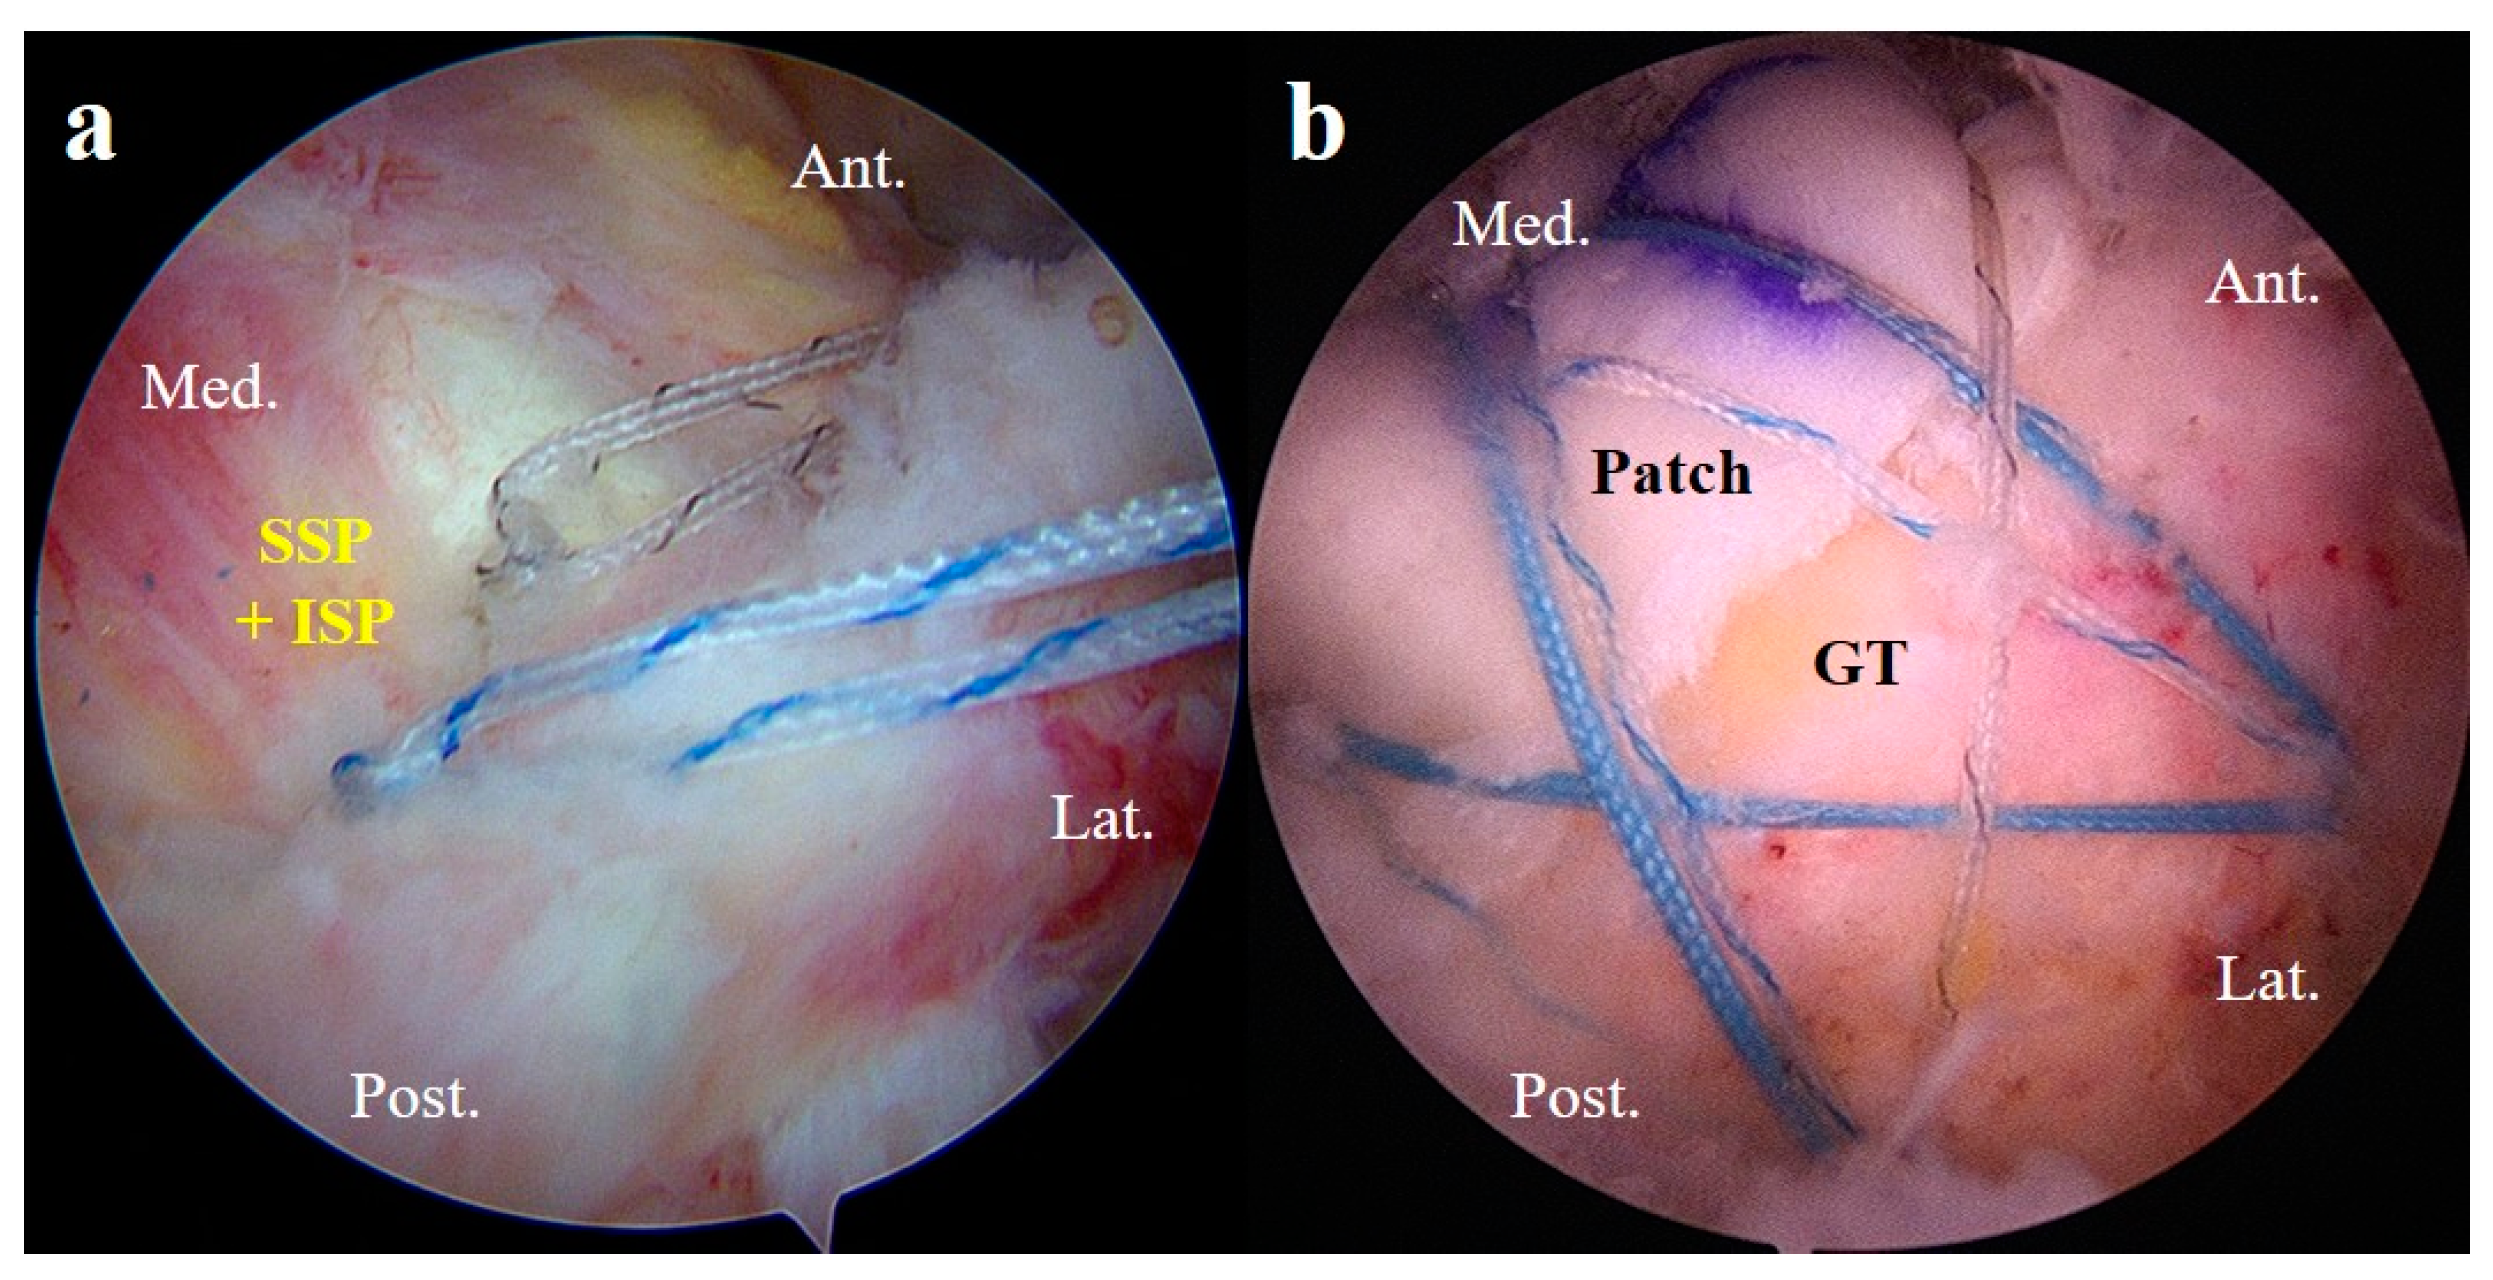

2.5.3. Patch Graft Augmentation